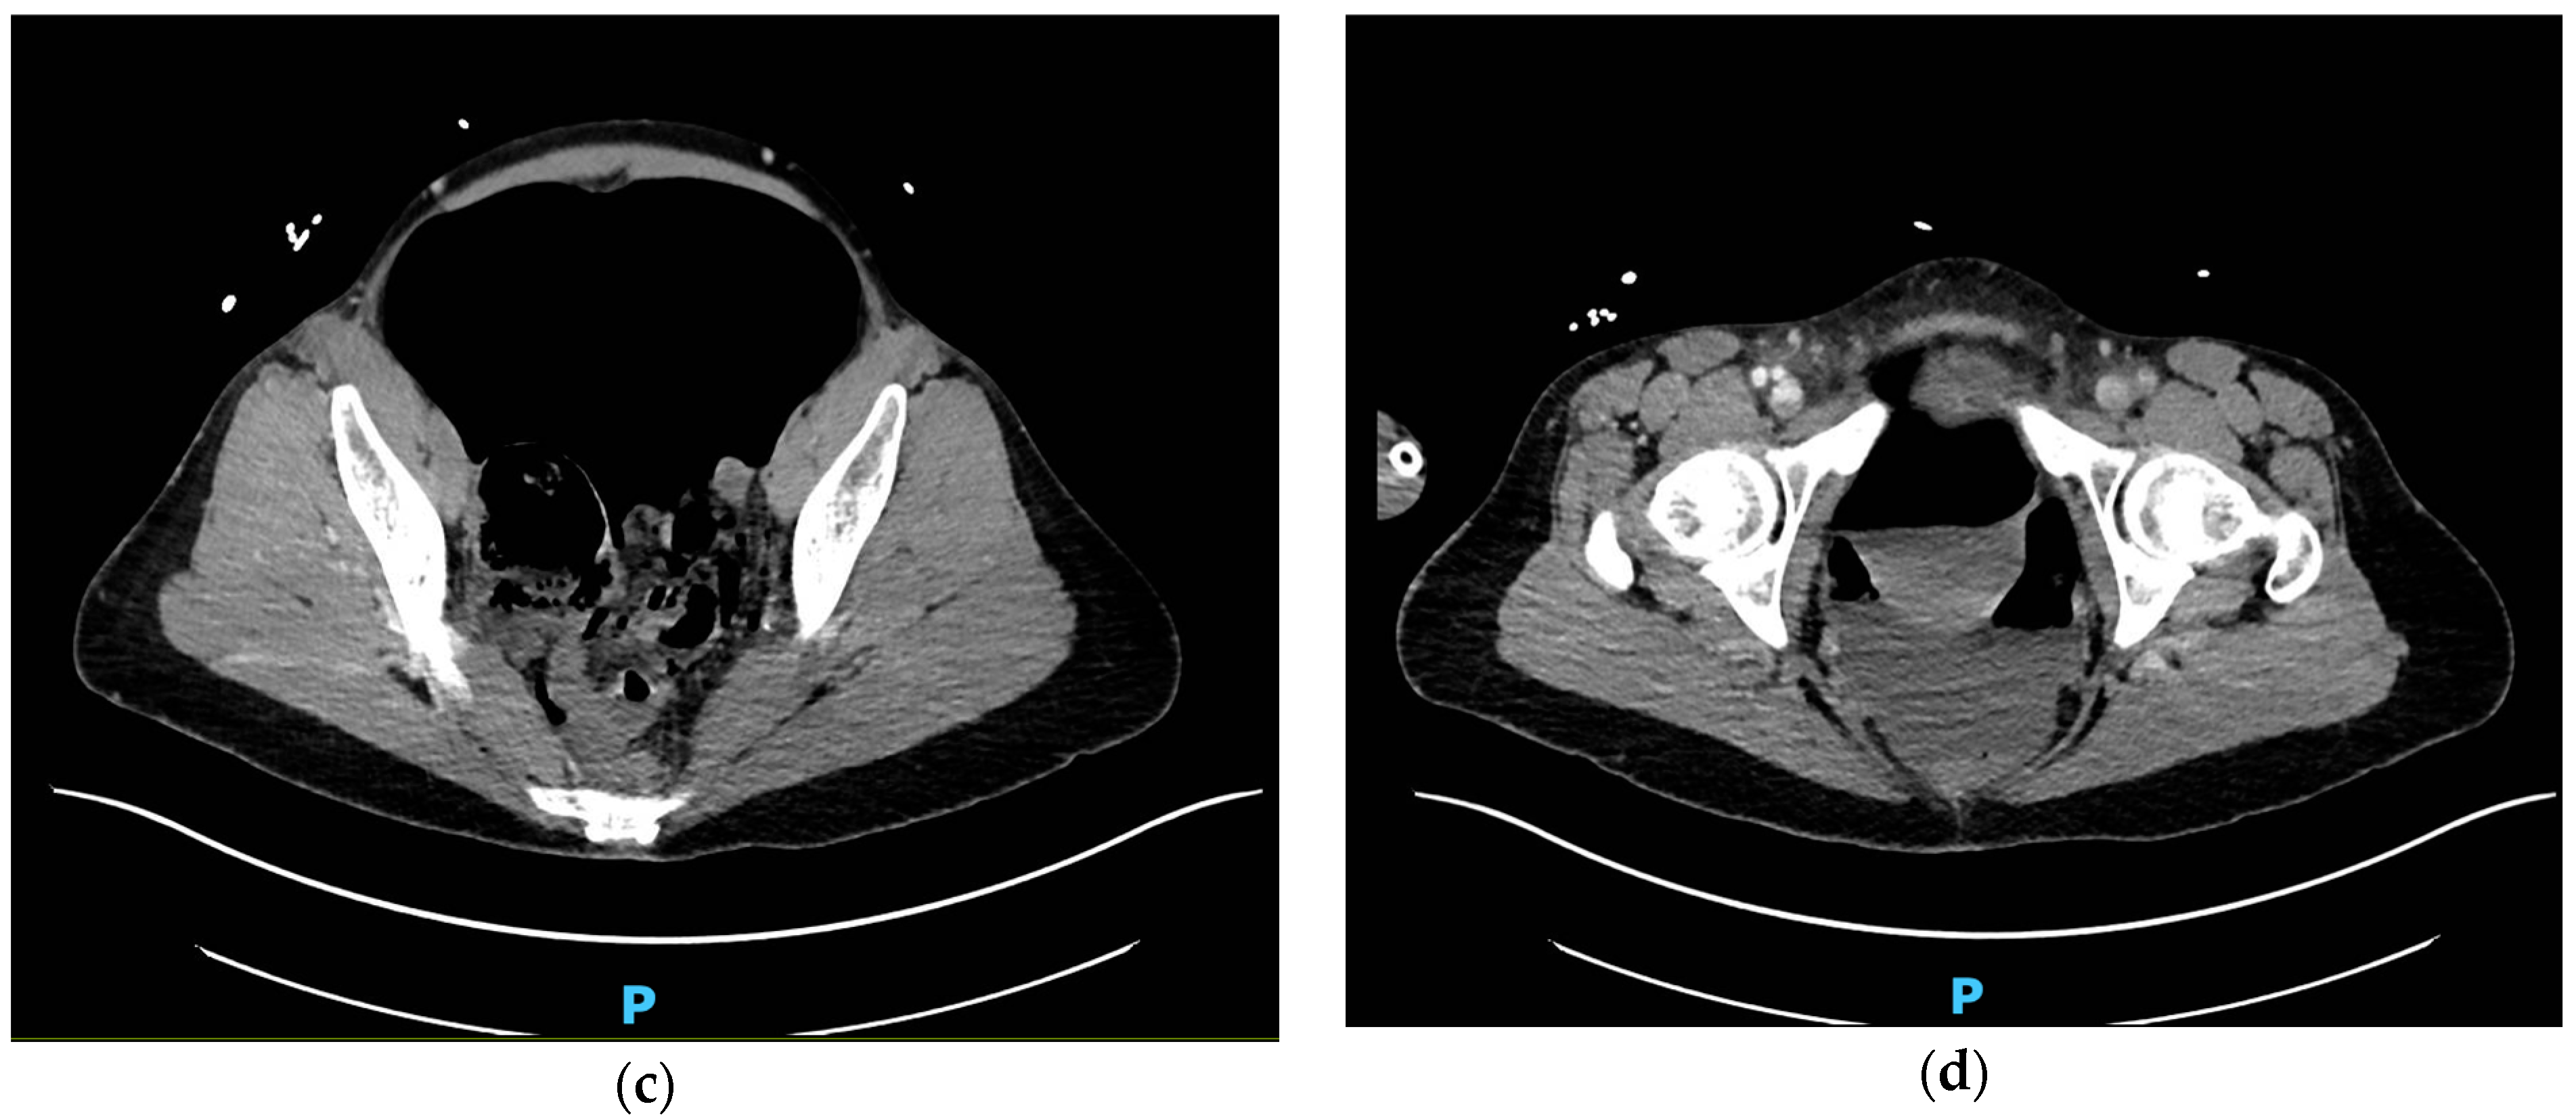

Upon arrival in the ED, patient was combative. Initial vitals were within normal limits, including a blood pressure of 110/70 and heart rate in 70 s. Urine and serum toxicology tests were positive for cocaine, hydrocodone, cannabinoids, and alcohol (serum level 312 mg/dL). She was found to have a significantly distended abdomen described as “rock-hard” to palpation. A lower extremity exam revealed dusky appearing feet that were cool to touch, non-palpable or dopplerable dorsalis pedis pulses, and 1+ radial pulses bilaterally. Bedside ultrasound revealed air in all abdominal quadrants. Subsequent expedient computed tomography angiography (CTA) revealed tension pneumoperitoneum with compression of the vena cava and aorta and presence of pneumatosis intestinalis diffusely throughout the small bowel (Figure 1a–d).

Figure 1.

Computed tomography angiography taken in the emergency department of the patient’s abdomen from superior (a) to inferior (d); (a) diffuse wall thickening with pneumatosis of multiple small bowel loops; (b) large volume pneumoperitoneum is shown to measure 11.34 cm in width and compress posterior structures, including abdominal aorta, via mass effect; (c) pneumoperitoneum is shown occupy over half of the cross-sectional area of the abdominal cavity; (d) mass effect from pneumoperitoneum is shown to compress organs all the way in the pelvis.